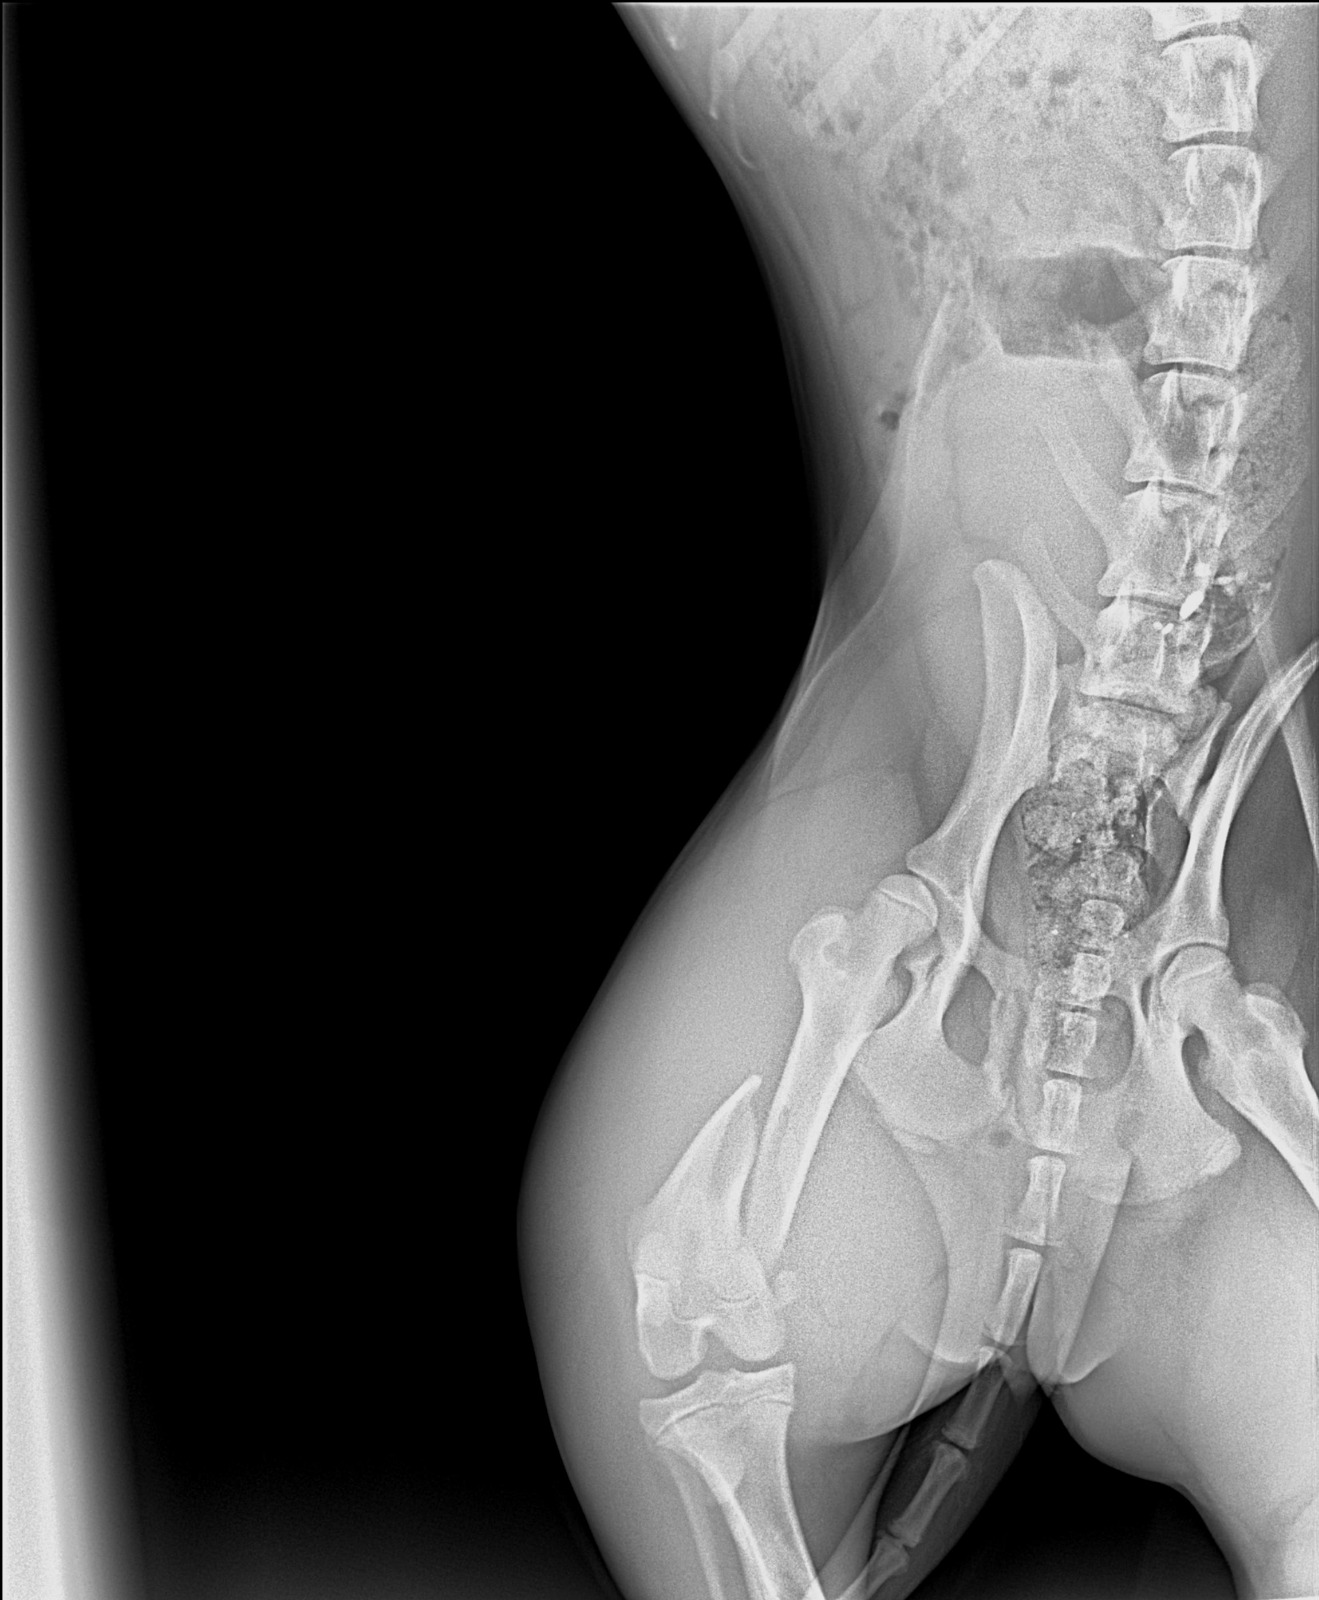

These dogs are in south lebanon rescued from war zone after being left behind. The one to the left was hit by a car and have a broken hip as shows frkm x rays and needs an urgent operation. It costs 650 usd as per the screenshot of chat with the vet. Please your help us needed. We can not afford as we are not working currently.